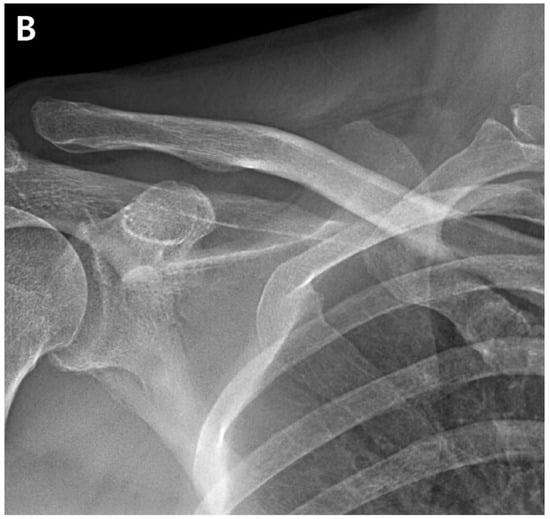

The ACR was performed in the lateral decubitus position under general anesthesia. The fluid used during the surgery was mixed with 1 mg of epinephrine per 3 L of normal saline, and the water pressure was maintained at 30–50 mmHg using an automatic infuser (10 K Fluid System, ConMed Linvatec, Largo, FL, USA). No abnormalities were observed in the rotator cuff, biceps long-head tendon, or glenohumeral joints upon arthroscopic examination. The ACR was performed according to the regular sequence, starting with the release of the rotator interval, middle glenohumeral ligament, and inferior and posterior capsules using a 3.0 mm 90° electrocautery device (Arthrocare, Smith & Nephew, Memphis, TN, USA) (Figure 2). After the ACR, the ROM under general anesthesia was defined as 150° forward flexion, 150° abduction, at the level of the eighth thoracic vertebral body for internal rotation, and 80° external rotation.

Figure 2.

Arthroscopic capsular release was performed. (A). Release of the thickened middle glenohumeral ligament was performed. (B). The inferior capsule was released using a radiofrequency ablation device. (C). Engorgement synovitis and capsule thickening were observed.